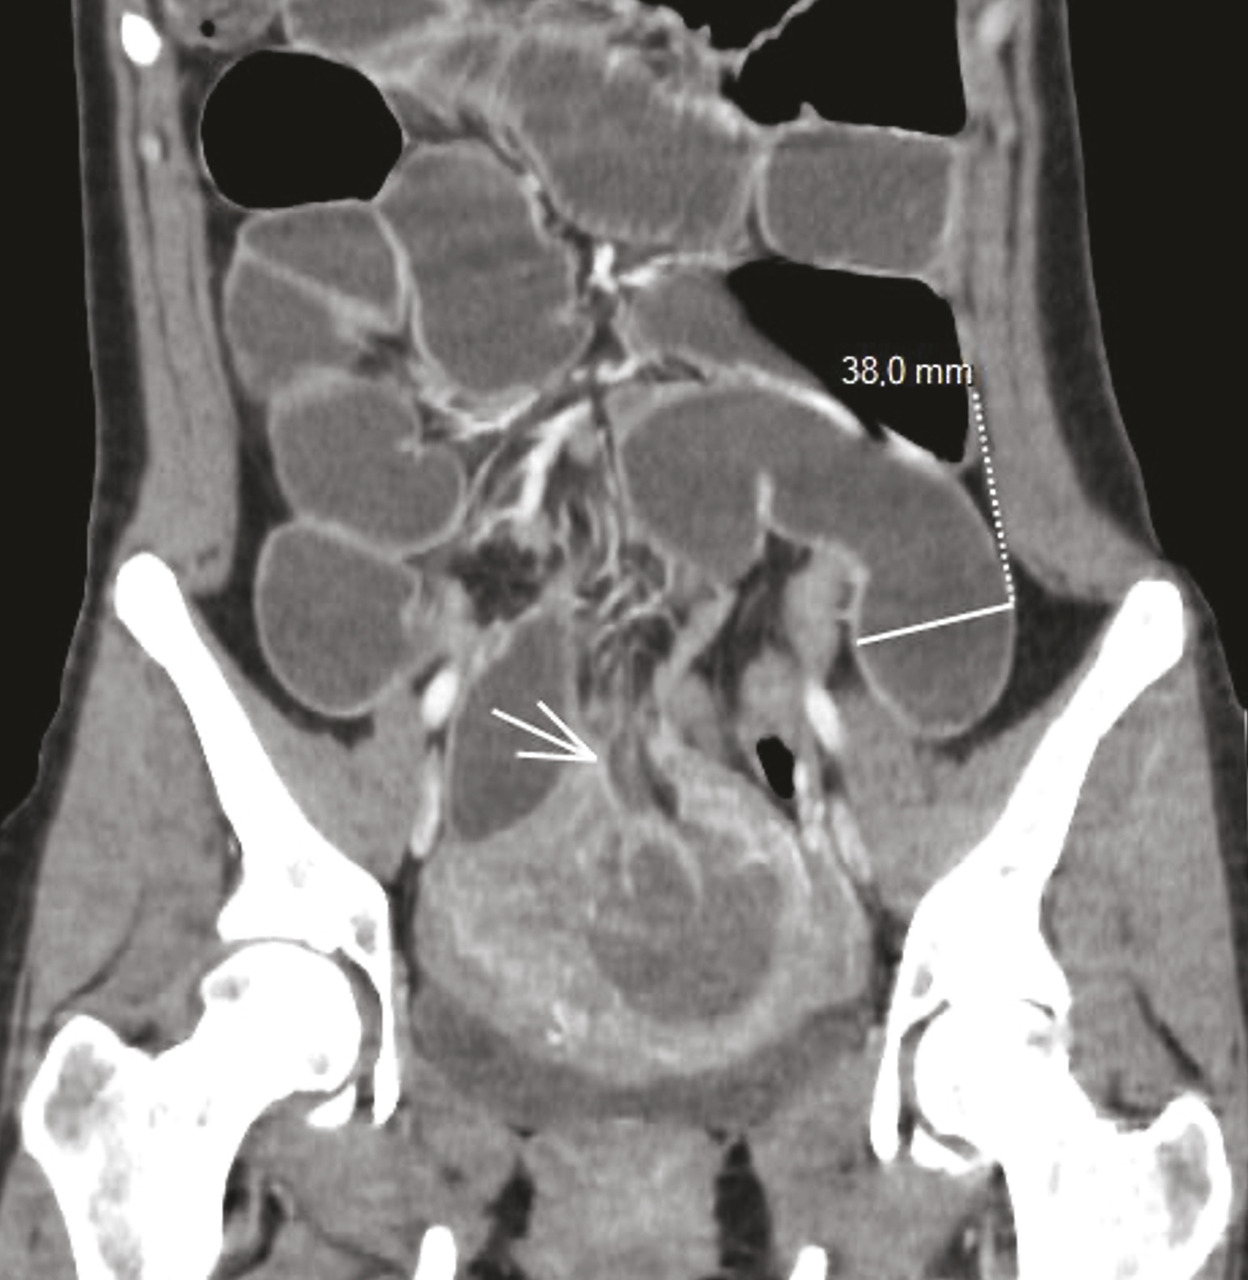

Le scanner (fig. 1 ) et l’imagerie par résonance magnétique (IRM) [fig. 2 ] montrent un défect pariétal du fond utérin avec incarcération d’une anse intestinale en position intra-utérine qui semble discontinue, avec un contenu hématique en hypersignal T1 et une distension de l’intestin grêle d’amont à contenu hydro-aérique, ainsi qu’un épanchement liquidien intrapéritonéal.

Le scanner (